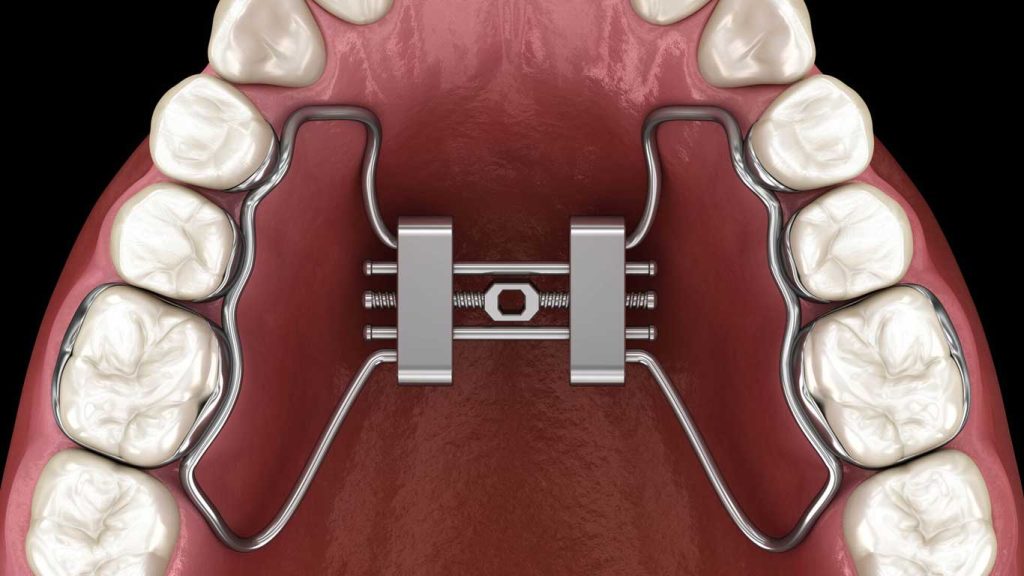

وسیع کننده کام یا پالاتال اکسپندر یک دستگاه ارتودنسی است که برای باز کردن عرض فک بالای بیماران طراحی شده است. این وسیله با ایجاد فشار کنترل شده روی دو نیمه فک بالا، به تدریج باعث گسترش استخوان و بهبود جایگاه دندان ها میشود.

وسیع کننده کام یا پالاتال اکسپندر با فشارهای ملایم ولی مداوم به استخوان فک بالا عمل میکند. این فشار باعث میشود که درز میانی فک، که در سنین رشد هنوز انعطاف دارد، به تدریج باز شده و فضای بیشتری ایجاد شود.

انواع وسیع کننده های کام

وسیع کننده های کام در دو نوع ثابت و متحرک وجود دارند. نوع ثابت به دندان ها متصل شده و نیاز به تنظیمات دستی روزانه دارد، در حالی که نوع متحرک را میتوان برای راحتی خارج کرد و نیازمند همکاری دقیق بیمار است.

معرفی رایجترین مدل های وسیع کننده کام یا پالاتال اکسپندر

از رایجترین مدل های وسیع کننده کام یا پالاتال اکسپندر میتوان به “هاس اکسپندر”، “هاید اکسپندر” و “کواد هلیکس” اشاره کرد. هر کدام از این مدل ها بسته به شرایط بالینی بیمار و تشخیص متخصص ارتودنسی انتخاب میشوند.